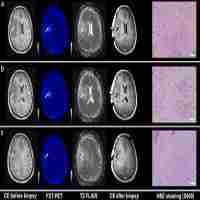

| Abstract | Neuroimaging based on O-(2-[18F]fluoroethyl)-L-tyrosine (FET)-PET provides additional information on tumor grade and extent compared to MRI. Dynamic PET for biopsy target selection further improves results but is often clinically impractical. Static FET-PET performed at two time-points may be a good compromise, but data on this approach are limited. The aim of this study was to compare the histology of lesions obtained from two challenging glioma patients with targets selected based on hybrid dual time-point FET-PET/MRI. Five neuronavigated tumor biopsies were performed in two difficult cases of suspected glioma. Lesions with (T1-CE) and without contrast enhancement (T1 and T2-FLAIR) on MRI were selected. Dual time-point FET-PET imaging was performed 5-15 minutes (PET10) and 45-60 minutes (PET60) after radionuclide injection. The most informative FET-PET/MRI images were co-registered with MRI in time of biopsy planning. Five biopsy targets (three from high uptake and two from moderate uptake FET areas) thought to represent the most malignant sites and tumor extent were selected. Histopathological findings were compared with FET-PET and MRI images. Increased FET uptake in the area of non-CE locations on MRI correlated well with high grade gliomas localized as far as 3 cm from T1-CE foci. Selecting a target in the motor cortex based on FET kinetics defined by dual time-point PET resulted in a grade IV diagnosis after previous negative biopsies based on MRI. An additional grade III diagnosis was obtained from an area of glioma infiltration with moderate FET uptake (between 1-1.25 SUV). This findings seem to show that dual time-point FET-PET-based biopsies can provide additional and clinically useful information for glioma diagnosis. Selection of targets based on dual time-point images may be useful for determining the most malignant tumor areas and may therefore be useful for resection and radiotherapy planning. |